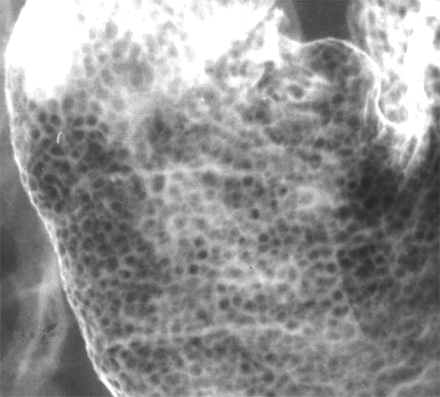

DDx or Stomach filling defects.

Primary Malignant Neoplasms:

Polyps:

Submucosal:

Extrinsic Indentation:

Others: